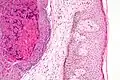

Histologically, molluscum contagiosum is characterized by molluscum bodies (also known as Henderson-Patterson bodies) in the epidermis, above the stratum basale, which consist of cells with abundant large granular eosinophilic cytoplasmic inclusion bodies (accumulated virions) and a small nucleus that has been pushed to the periphery.[19][20]

Low magnification micrograph of a molluscum contagiosum lesion -

Low-magnification micrograph of molluscum contagiosum, H&E stain -

High-magnification micrograph of molluscum contagiosum, showing the characteristic molluscum bodies, H&E stain